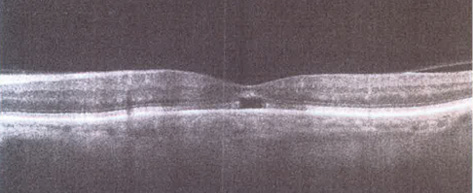

Figure 2. Spectral-domain OCT image shows presence of microhole (outer lamellar defect).

Microhole

A microhole may not be detected in the presence of a moderate to severe cataract. Postoperative vision can be 20/20 despite a microhole, although the patient may complain of “imperfect vision.” OCT examination is useful in diagnosing the breach in the outer retinal structures (Figure 2).